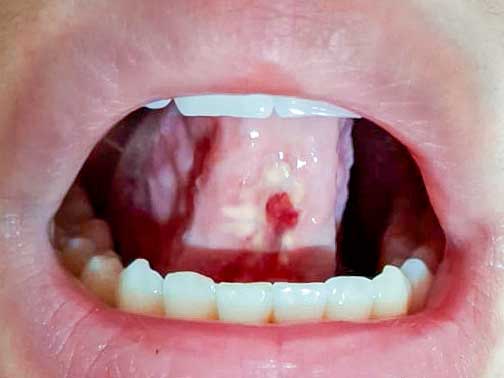

Resección frenillo lengua

Severa limitación en motilidad lingual

Al examen clínico se observó un frenillo lingual de inserción corta, con restricción mecánica marcada y compromiso funcional evidente.